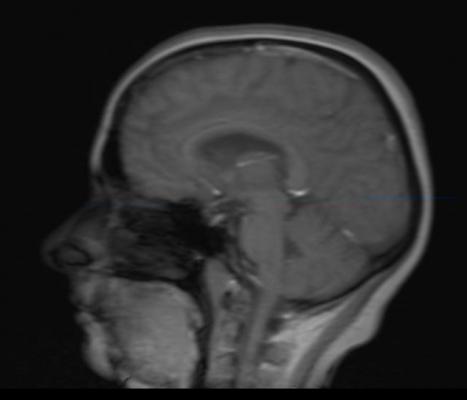

April 13, 2016 — As chronic traumatic encephalopathy (CTE) stands in the national spotlight for high impact sports, the University of California, Irvine has partnered with Toshiba America Medical Systems Inc. for a first-of-its-kind study of cerebral microbleeds (CMB) in high school football players as a potential precursor to CTE. The study will utilize Toshiba’s Vantage Titan 3T magnetic resonance (MR) system as the key diagnostic tool, taking advantage of its non-invasive capabilities.

The study will investigate the use of non-contrast MRI as a safe and noninvasive way to examine youth athletes and other patients for early signs of CTE, a degenerative disease found in those who suffer head trauma and a well-documented consequence of sub-concussive head injury. This will include evaluations of local high school student volunteers, including 100 test subjects (football players) and 50 control subjects (non-football players). Toshiba will provide application training to UCI researchers concerning the use of Toshiba’s MRI equipment.

The Vantage Titan 3T MR was chosen for its ability to provide non-contrast neuro imaging. This includes elements such as a suite of advanced neuro-imaging sequences and Pianissimo noise-reduction technology, and in particular its ability to determine the prevalence of CMB using the Flow Sensitive Black Blood (FSBB) sequence.